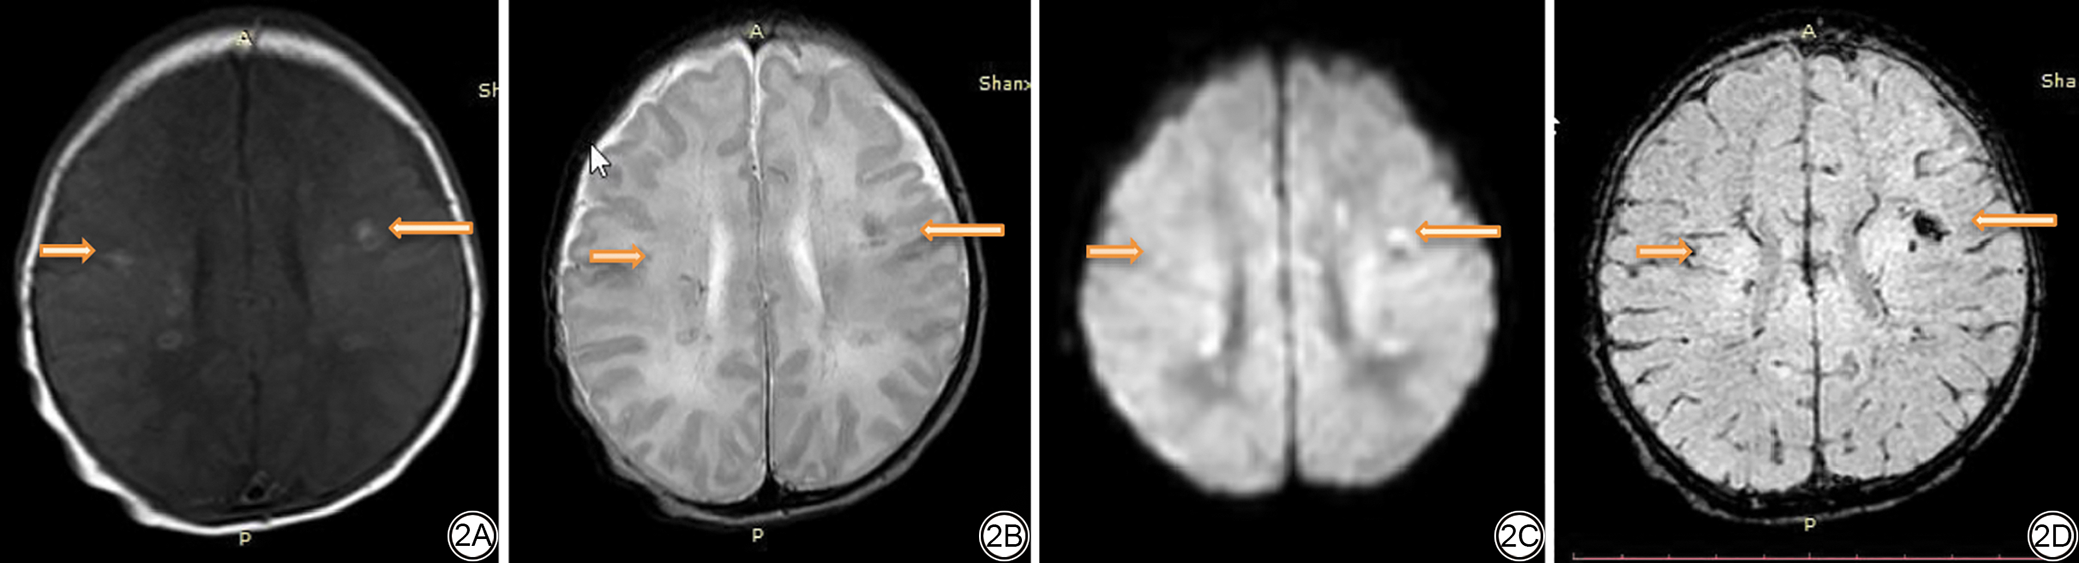

图2  女,胎龄39周,肩难产。2A示T1WI双侧侧脑室旁白质内斑片状高信号;2B示T2WI双侧侧脑室旁白质斑片状低信号;2C示DWI序列相应部位呈高信号,局部可见低信号;2D示SWI序列相应病灶呈低信号。提示PWML合并出血。T1WI:T1加权成像;T2WI:T2加权成像;DWI:扩散加权成像;SWI:磁敏感加权成像;PWML:局灶性脑白质损伤。

Fig. 2  Scans of a female (gestational age = 39 weeks) with shoulder dystocia. 2A: A patchy high signal in bilateral paraventricular white matter on TIWI; 2B: A patchy low signal was seen in the bilateral paraventricular white matter on T2WI; 2C: The corresponding areas on DWI sequence showed high and low signals; 2D: The corresponding lesions on SWI showed low signal intensity, suggestive of a PWML complicated by bleeding. T1WI: T1-weighted images; T2WI: T2-weighted images; DWI: diffusion-weighted imaging; SWI: susceptibility-weighted imaging; PWML: punctate white matter lesion.